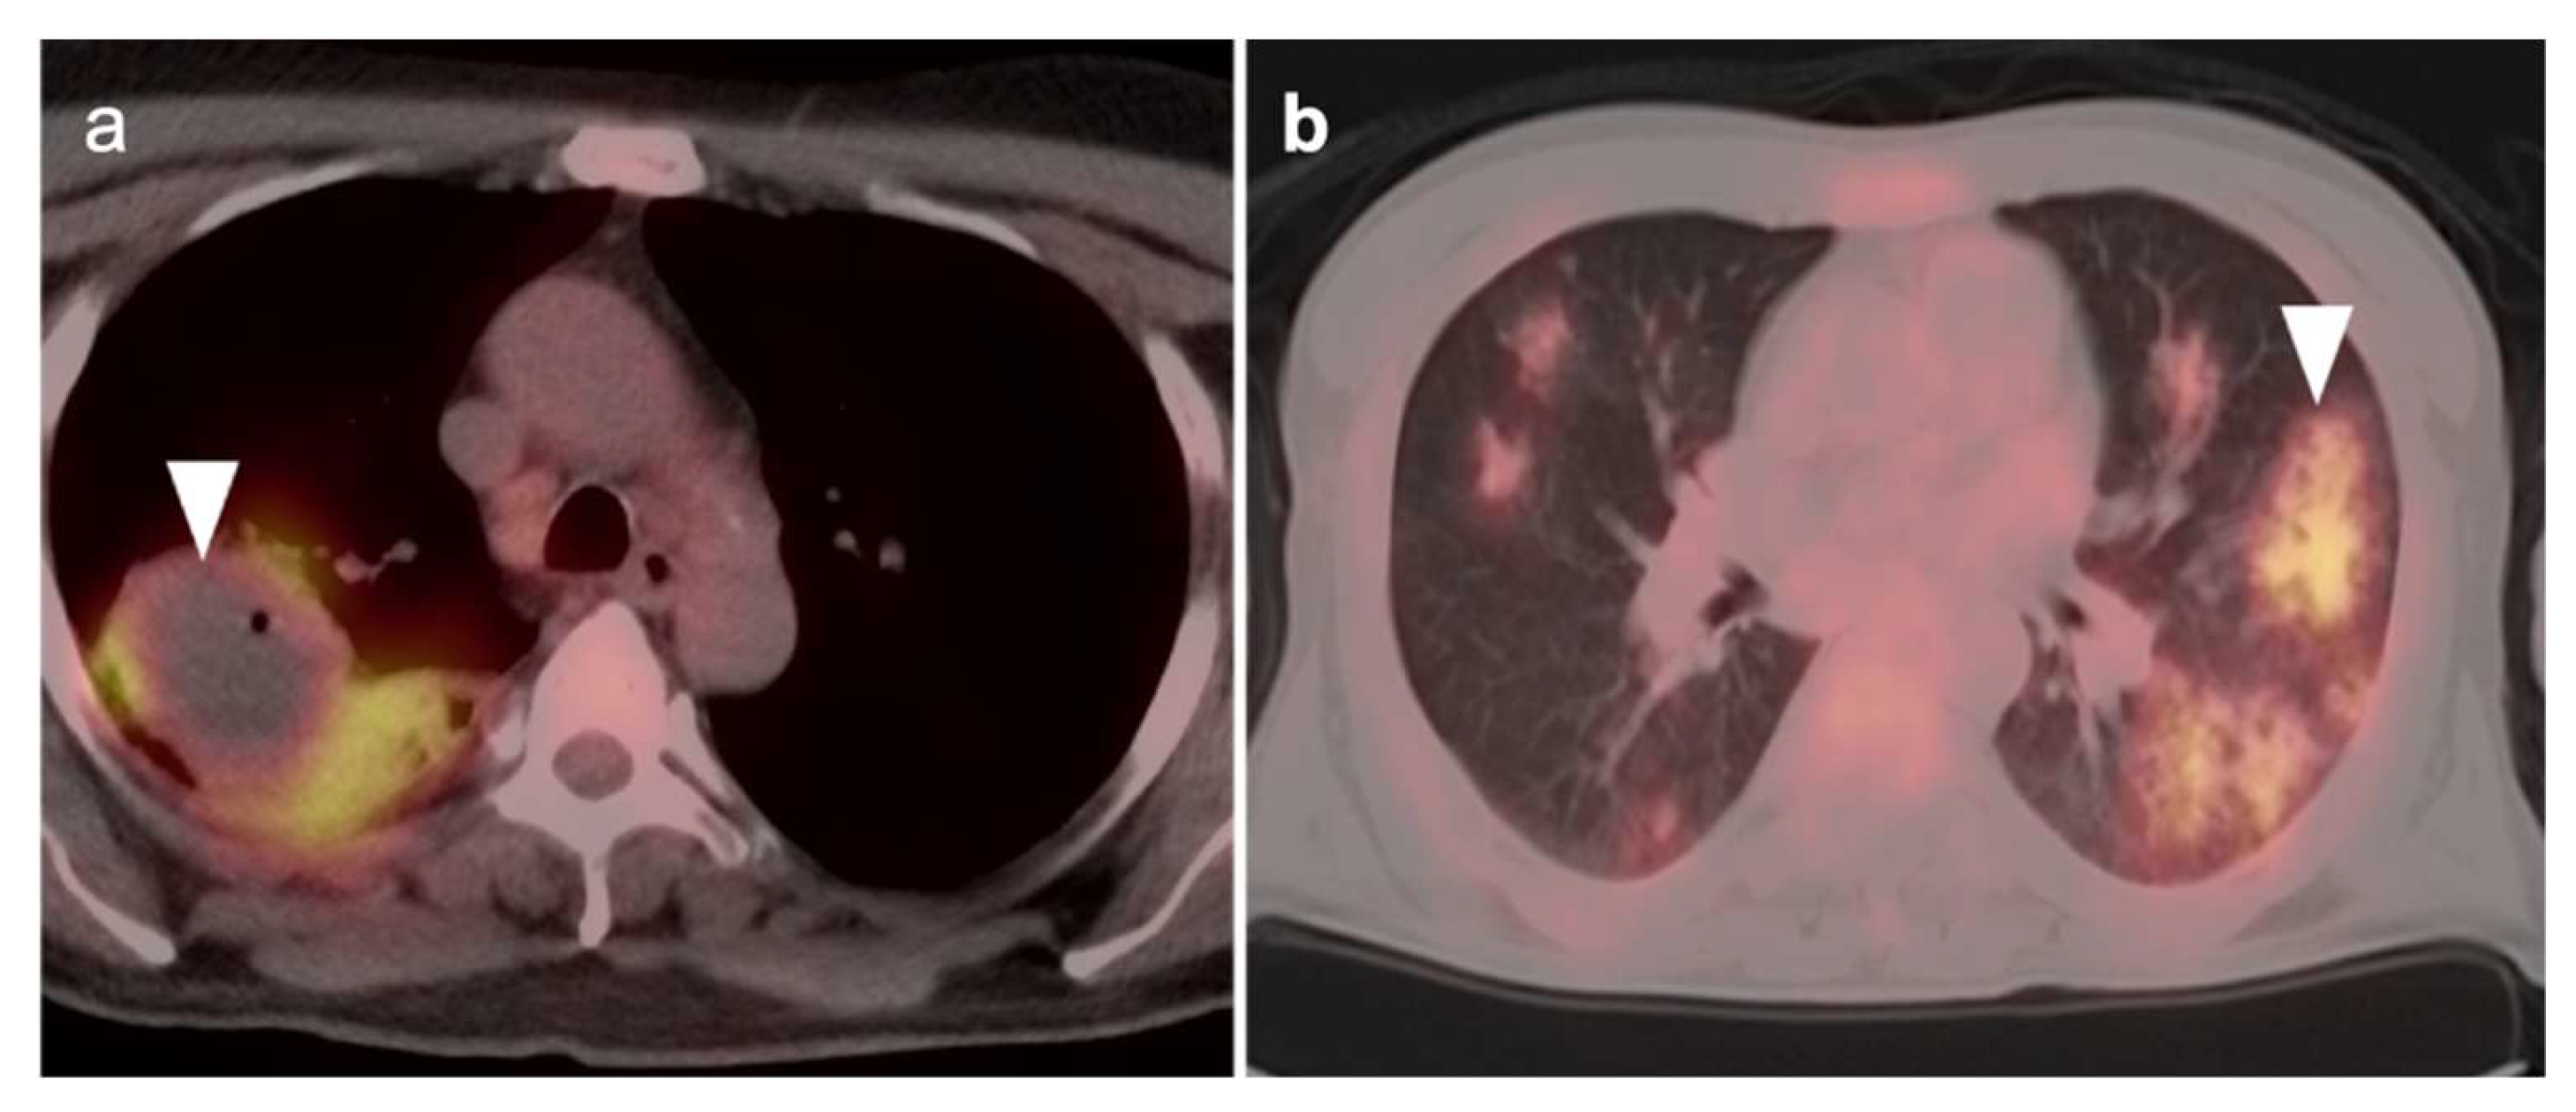

5.5. Invasive Ductal Carcinoma

The most common subtype of breast cancer is invasive ductal carcinoma (IDC) which accounts for most invasive breast cancer diagnoses [93,108] Invasive ductal carcinoma characteristically shows abnormal uptake on FDG PET-CT imaging and demonstrates higher uptake levels with larger tumors, higher grade tumors, metaplastic tumors, hormone receptor negative tumors, and triple-negative tumors (Figure 20) [109,110,111]. On FES PET-CT imaging, invasive ductal carcinoma would typically show uptake if the IDC is ER+. FES PET-CT may also depict heterogeneous ER expression in cases of metastatic IDC, wherein some but not all tumors have functional ERs. Invasive ductal carcinoma may be identified at a higher rate on FDG PET-CT imaging compared to invasive lobular carcinoma, discussed further below [110].